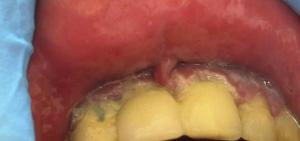

Первичный сифилис начинается с появления первичного сифилитического высыпания – твердого шанкра.

На губах, твердый шанкр может проявляться в различных формах:

Ключевые Характеристики Твердого Шанкра на Губах:

- Эрозивная форма: Наиболее частая форма. Представляет собой безболезненную, округлую эрозию. Края четкие, приподнятые. Дно эрозии покрыто серозным или кровянистым отделяемым. Размер эрозии варьирует от нескольких миллиметров до 1-2 сантиметров в диаметре. Цвет эрозии обычно бледно-красный.

- Безболезненность: Основной отличительный признак твердого шанкра.

- Твердость высыпания: Характерной особенностью является уплотнение в поражения. Это связано с развитием воспаления тканей.

Изменения могут располагаться как на внешней, так и на внутренней стороне губ, в уголках рта, по краю губ.

На начальной стадии на губе появляется пятно, в центре которого происходит распад тканей.

Со временем образуется язва с ровными краями и гладким дном.

Она увеличивается и может достигать 2 см в диаметре.